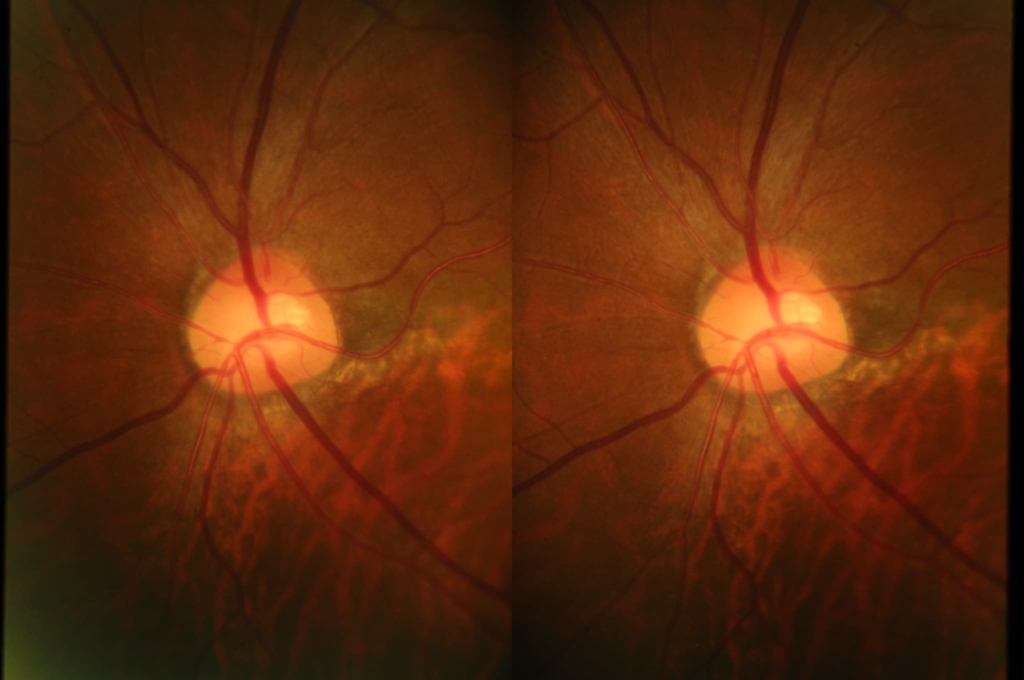

乳頭が下鼻側に傾斜し、下方に萎縮(PPA)がみられる。

両眼ともに、後部ぶどう腫staphylomaの上縁に一致して乳頭下縁から黄斑を横断するように帯状の網脈絡膜の萎縮巣がみられる。また後部ぶどう腫領域に一致して網膜・脈絡膜が菲薄化しているため、紋理眼底tessel lated fundusがみられる。